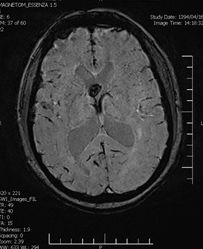

Background: Cavernous hemangiomas are common benign vascular malformations. Their existence in the intraventricular region is very rare. Case Reports: A 43-year old woman with an occipital headache was admitted to the emergency ward. Brain computed tomography scan showed mild hydrocephalus and multiple intraventricular isodense lesions. Imaging findings, especially of Gradient Resonance Echo imaging, were in favor of multiple intraventricular cavernous malformations. Conclusion: This is a rare presentation of multiple cavernous malformation as occipital headache without needing surgical intervention in this phase. Coexistence of periventricular plaques like Radiologically isolated syndrome of Multiple sclerosis is another unique aspect in this report. [GMJ.2017;6(1):61-65]